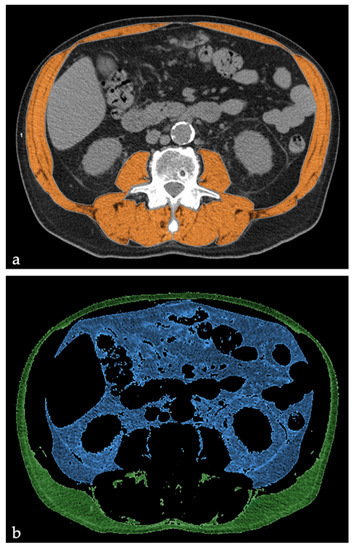

2.1. Body Composition Parameter Measurements